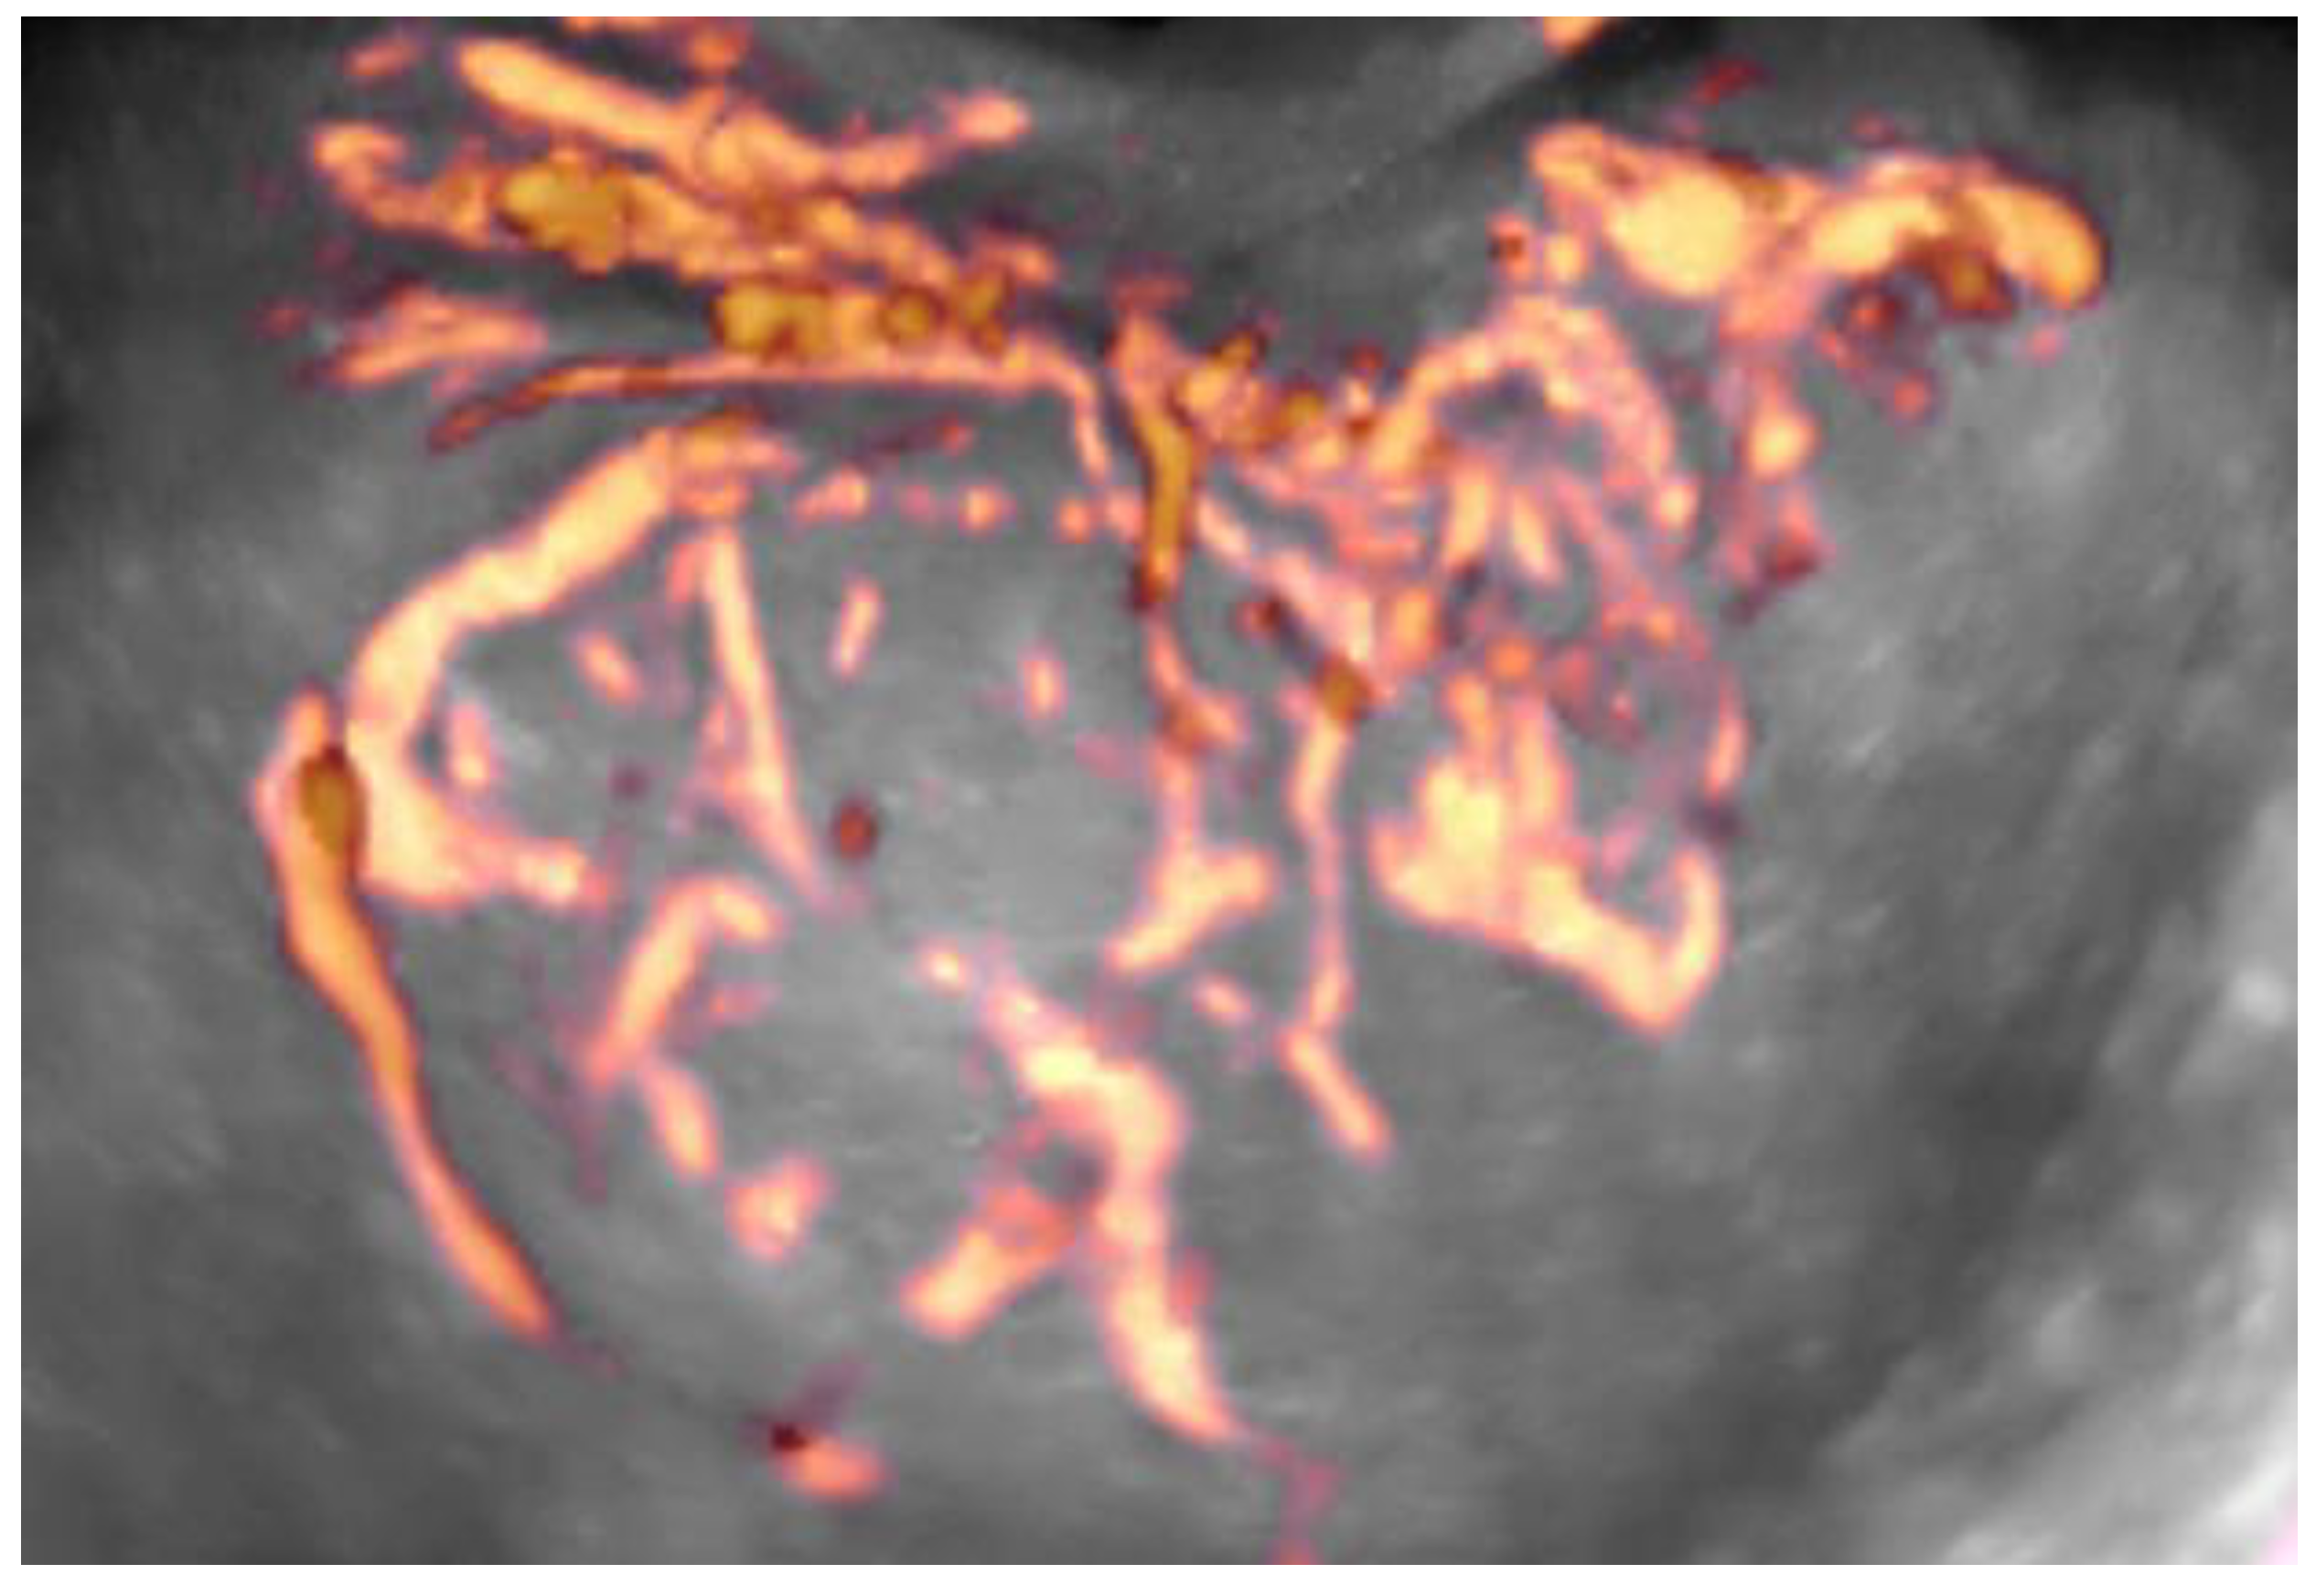

4D Doppler Ultrasound in High Grade Serous Ovarian Cancer Vascularity Evaluation—Preliminary Study